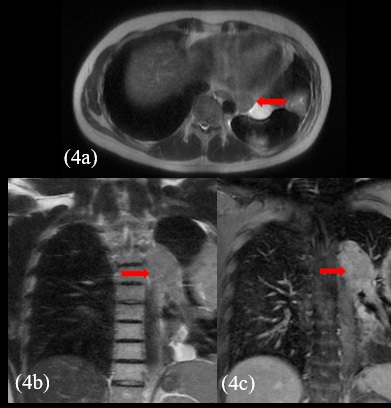

The patient presented with voluminous and symptomatic disease less than six months of chemotherapy end and less than two months of radiotherapy. He restarted with pain in left hemithorax, cough, shortness of breath, lack of appetite and daily vespertine fever. MRI scans in August, 2021 showed new lesions on pleural surfaces beyond the residual mass previously seen (Figures 4a, 4b and 4c). One of the lesions, on the extra-pleural fat adjacent to the diaphragm, extended inferiorly, pushing downward the muscle.